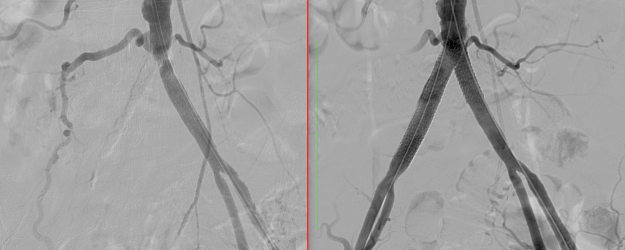

Αγγειοπλαστική “φίστουλας” (fistula) αιμοκαθαιρόμενου νεφροπαθούς ασθενούς – διάσωση παλαιάς φίστουλας με μπαλονάκι – μία σύγχρονη τεχνική αντιμετώπισης στενώσεων, υπερπλασιών αρτηριοφλεβικής επικοινωνίας σε ασθενείς που υποβάλλονται σε αιμοκάθαρση. Για την αγγειοπλαστική χρησιμοποιείται μπαλόνι υψηλών πιέσεων ή φαρμακευτικό μπαλόνι (φαρμακευτική ουσία που εναποτίθεται στο τοίχωμα του αγγείου μειώνοντας την πιθανότητα γρήγορης υπερπλασίας-επαναστένωσης). Η παρέμβαση γίνεται υπό τοπική…